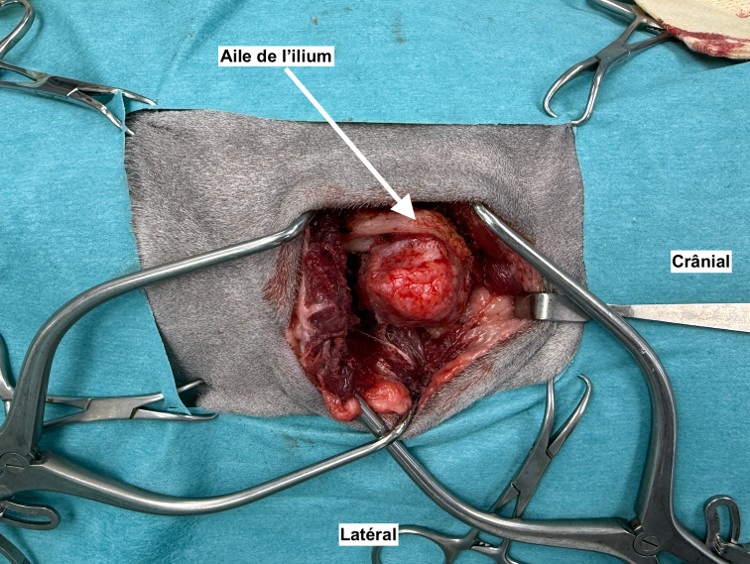

Trois cas résultent de l'extension d'une otite. Ces patients étaient présentés pour ataxie et l'un d'entre eux présentait également des crises convulsives partielles. Dans les trois cas, un examen scanner a mis en évidence une otite moyenne associée à une lésion intracrânienne extra-axiale adjacente, évoquant un empyème méningé. Dans le premier cas, un traitement antibiotique probabiliste permet la résolution des signes cliniques. Dans le deuxième cas, des prélèvements par vidéo-otoscopie permet d'identifier la présence de Staphylococcus felis. Un traitement antibiotique ciblé entraîne la résolution des signes cliniques. Dans le troisième cas, l'examen vidéo-otoscopique permet l'identification de Pseudomonas spp. Malgré une antibiothérapie adaptée, l'état clinique du patient se détériore. Un nouvel examen scanner montre une aggravation de l'empyème méningé. Une craniotomie est réalisée et permet le débridement de l'empyème. Cette intervention, associée à une corticothérapie et la poursuite de l'antibiothérapie, permettent la résolution des signes cliniques.